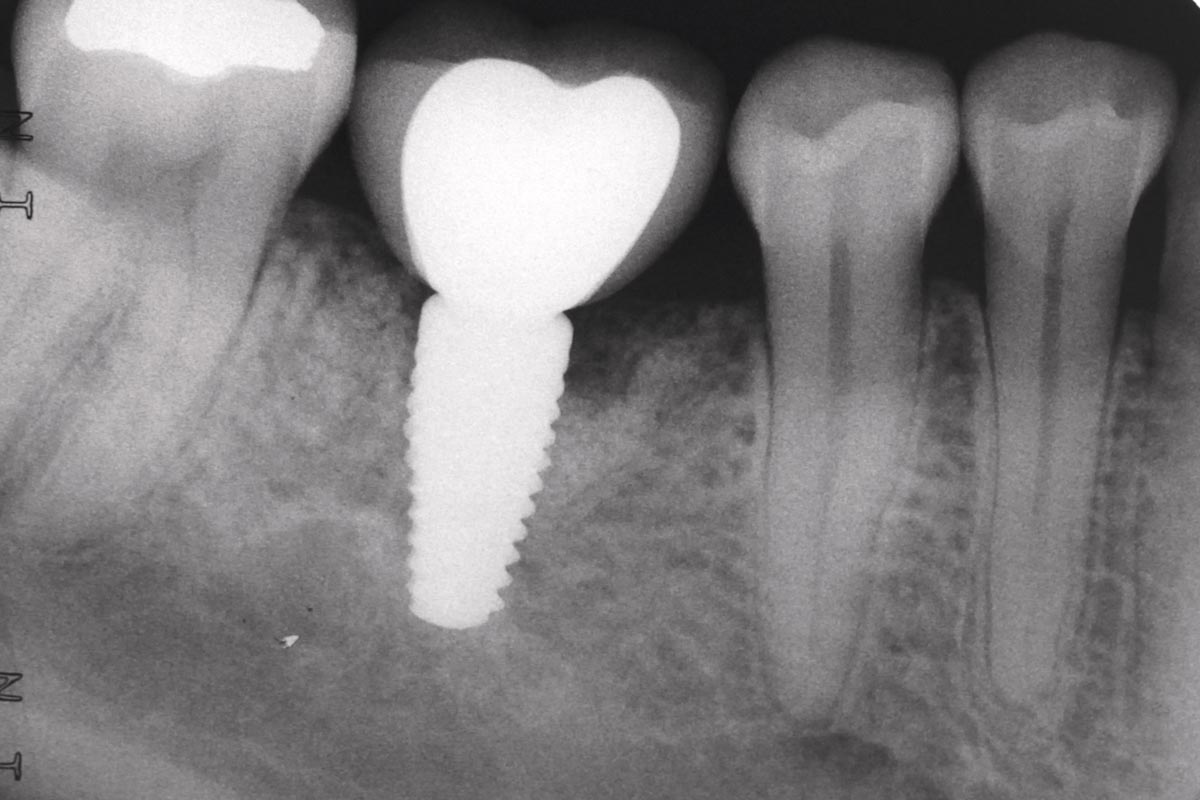

The patient presented with a terminal fracture of the crown tooth number 12